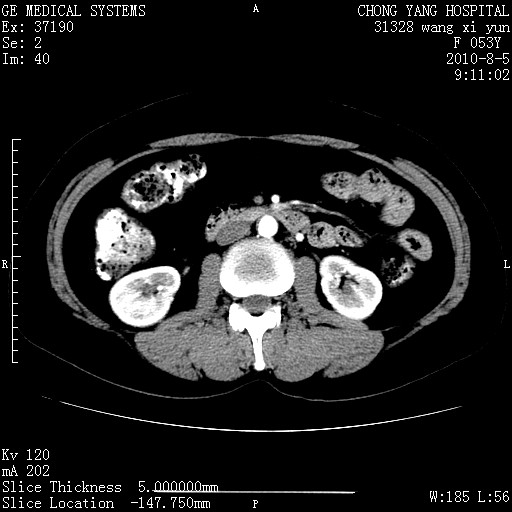

标题: CT28214:F41Y 血尿二十天,建议盆腔平扫加增强。

1)考虑肝左叶胆管细胞癌。2)脂肪肝。

支持胆管细胞ca。